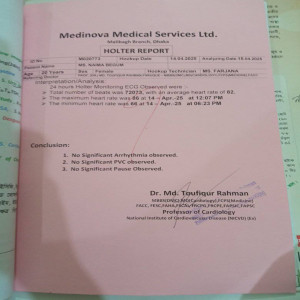

#250927A: হৃদরোগে আক্রান্ত আব্দুর রহমান তাবিদের ওপেন হার্ট সার্জারির জন্য সাহায্যের আবেদন, গ্রাম: বিন্নাটি, জেলা: কিশোরগঞ্জ।।